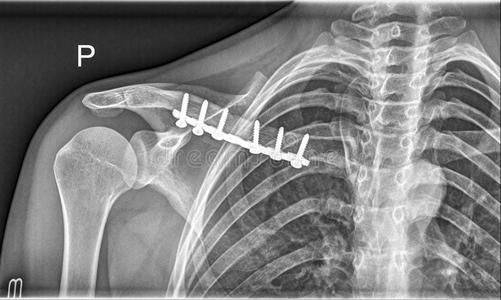

锁骨肩峰端骨折钩板固定

锁骨肩峰端骨折~锁骨钩板固定

锁骨肩峰端骨折,第一次使用钩钢板手术

术中选择了4孔,术中发现为锁骨肩峰端骨折,横行,骨折块较小,没固定